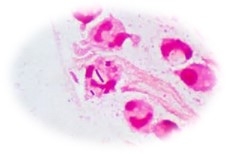

ダーマウェアの抗菌防臭機能

黄色ブドウ球菌を始め、大腸菌、肺炎桿菌、緑膿菌などのあらゆる雑菌の抑制します。

抗菌性は、染色の時に使われなったカチオン基が、逆性石鹸のような構造をしているため、菌の蛋白質に作用して抗菌性を発現します。